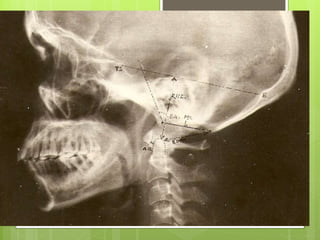

CRANIOMETRY:

 Craniometry of the CVJ uses a series of lines, planes &

angles to define the normal anatomic relationships of

the CVJ.

 These measurements can be taken on plain X rays,

3D CT or on MRI.

 No single measurement is helpful.

 disadvantage --anatomic structures and planes vary

within a normal range.

The important lines are

1. Chamberlain’s line

2. Wackenheim’s clivus

canal line

3. Mc Gregor’s line (basal

line)

4. Mc rae’s line ( foramen

magnum line)

5. Height index of Klaus

6. Boogard,s line

7. FISHGOLD’S DIGASTRIC

LINE

8. FISHGOLD’S BIMASTOID